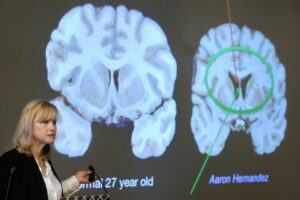

Shooter who targeted NFL headquarters diagnosed with CTE after death

The gunman who had suspected he had CTE when he shot several people in a Manhattan office building did in fact have the disease, the